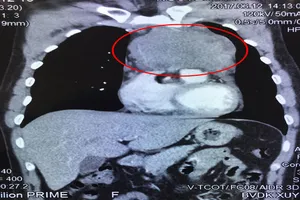

Phẫu thuật thành công khối u kích thước bằng quả cam trong lồng ngực Y tế - Sức khỏe 17/06/2017 19:02